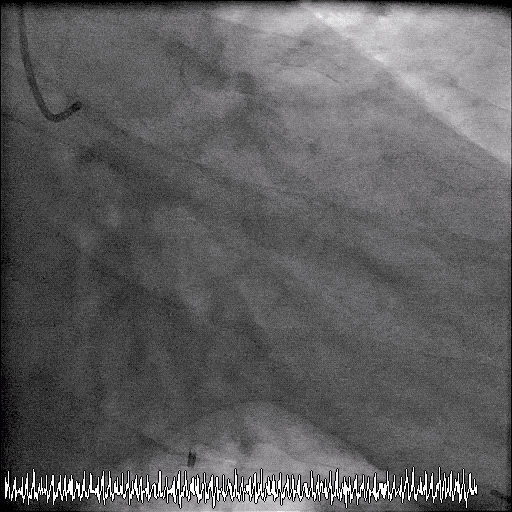

2. The LAD reaches the apex. A widely patent stent is seen. No in-stent stenosis.

6. Patent LAD stent.